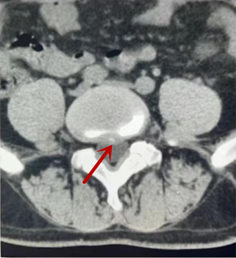

利器二:CT

CT利用X射線對(duì)人體檢查部位通過(guò)電腦切成若干層掃描,然后把每層的圖像都能顯示出來(lái)。CT相對(duì)于X光片具有更高的密度分辨力,可直接顯示X線片無(wú)法顯示的病變,觀察腰椎有無(wú)微小的骨折、骨質(zhì)有無(wú)破壞等骨質(zhì)情況、以及腰椎間盤(pán)突出、腰椎神經(jīng)根、椎管、椎間小關(guān)節(jié)的情況等。同時(shí)還可以通過(guò)后處理,重建腰椎矢狀位或冠狀位圖像,形成腰椎的3D圖像,更直觀地觀察病變部位,對(duì)腰椎手術(shù)風(fēng)險(xiǎn)具有提示作用,對(duì)手術(shù)方式的選擇具有指導(dǎo)意義,但是對(duì)神經(jīng)、脊髓損傷程度的顯示不如MRI,軟組織的分辨率仍有一定限制,對(duì)椎管內(nèi)病變顯示欠佳,且有一定的輻射。

箭頭提示椎間盤(pán)突出

從左向右依次為CT矢狀位重建圖像、三維重建圖像、軸位掃描圖像,箭頭提示腰1椎體爆裂性骨折